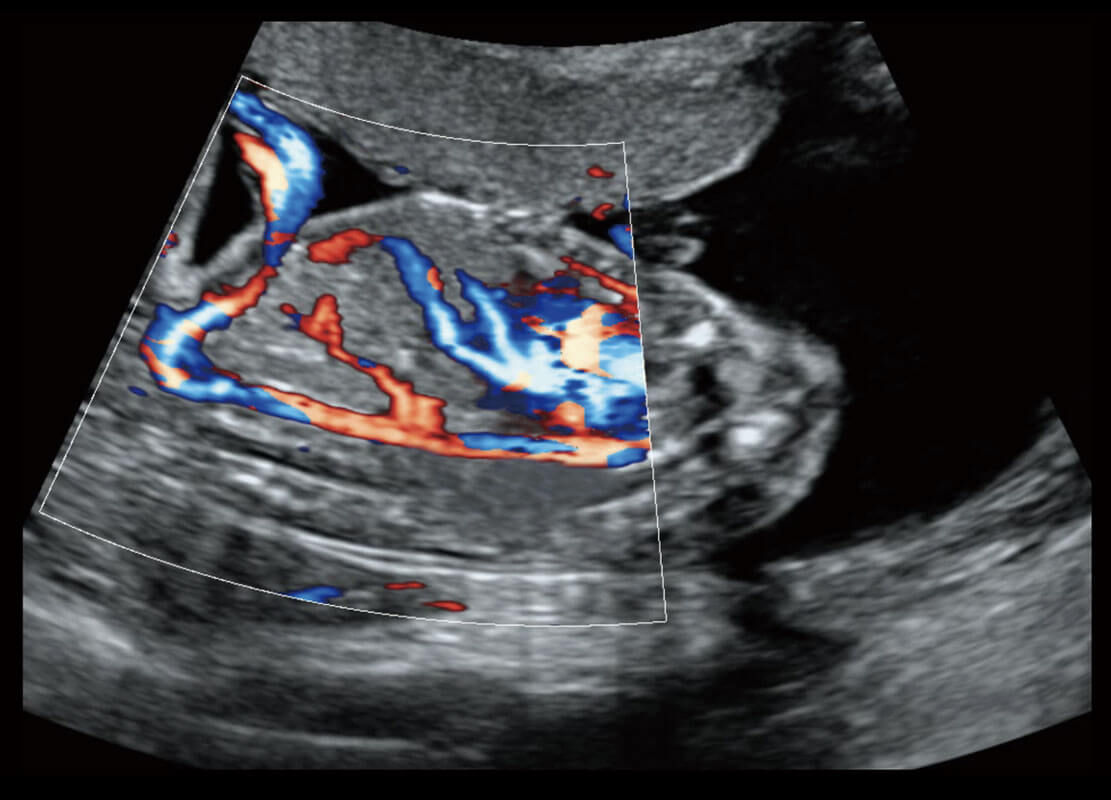

P60搭載一系列胎兒心臟成像技術(shù),實(shí)現(xiàn)精細(xì)的胎兒心臟評(píng)估。

四腔切面

四腔心血流

右室雙出口

胎心容積成像